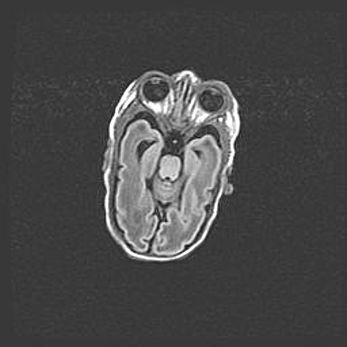

Мальформация Денди-Уокера. Киста задней черепной ямки.

Агенезия мозолистого тела.

Возраст: 2,5 месяца

Вес: 2420 г

Пол: женский

Окружность головы: 37 см

Срок гестации: 32 недели

Мальформация Денди—Уокера — редкий вид патологии ЦНС, представляющий собой врожденный порок развития каудального отдела ствола и червя мозжечка, ведущий к неполному раскрытию срединной (Мажанди) и латеральных (Лушка) апертур IV желудочка мозга. Для этогно синдрома характерна триада симптомов: гипотрофия червя мозжечка и/или полушарий мозжечка, кисты задней черепной ямки, гидроцефалия различной степени. В 70% случаев порок сочетается и с другими аномалиями головного мозга, в частности с агенезией мозолистого тела.